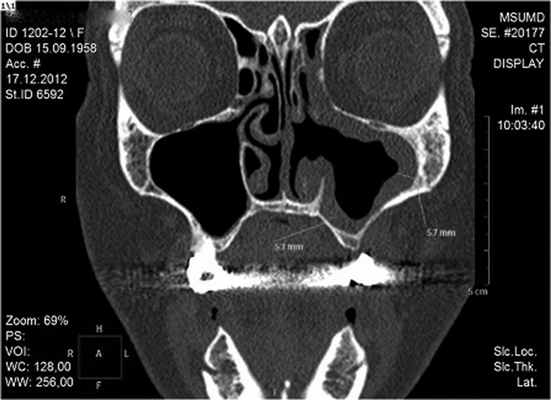

Через 10 дней после вмешательства у данной больной нами выполнено контрольное МСКТ-исследование средней зоны лица (рис. 3), Рисунок 3. Та же больная. МСК-томограмма в коронарной проекции через 2 нед после операции. По передней стенке левой ВЧП определяется послеоперационный костный дефект с четкими, ровными контурами. По всем стенкам левой гайморовой пазухи присутствует мягкотканный компонент(послеоперационные изменения), инородные тела отсутствуют. которое подтвердило полное удаление пломбировочного материала из верхнечелюстного синуса слева. Определяли признаки воспаления слизистой оболочки в прооперированной пазухе, являющиеся местной реакцией на проведенное вмешательство. Пациентка в срок наблюдения до 3 мес жалоб не предъявляла.